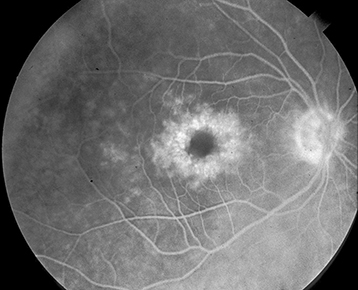

IVFA shows early leakage of perifoveal capillaries and late macular staining, classically in a petaloid or spoke-wheel pattern. Optic nerve head leakage is sometimes observed (particularly in inflammatory conditions such as IrvineGass syndrome). Fluorescein leakage does not occur in select cases of pseudo-CME (see above).